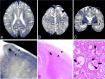

Case 2. A–C, Postmortem axial (A and B) and coronal (C) T2-weighted MR images show cortical laminar hyperintensities in the frontal lobes (B and C, arrows). Hyperintensities are also seen in the deep and subcortical white matters. D, Boxed area in panel C shows laminar hyperintensities in the deep layers of the cerebral cortex (arrowheads). E, The hematoxylin and eosin-stained section corresponding to panel D shows laminar pallor of the deep layers of the cerebral cortex (arrowheads). U-fibers are well preserved in this case (D and E, arrows). F, Histologic findings of the arrowhead area panel E shows spongy changes of the neuropil, pyknotic, and shrunken neurons (arrowheads) and Alzheimer type II astrocytes (arrows). (Hematoxylin and eosin ×100.)